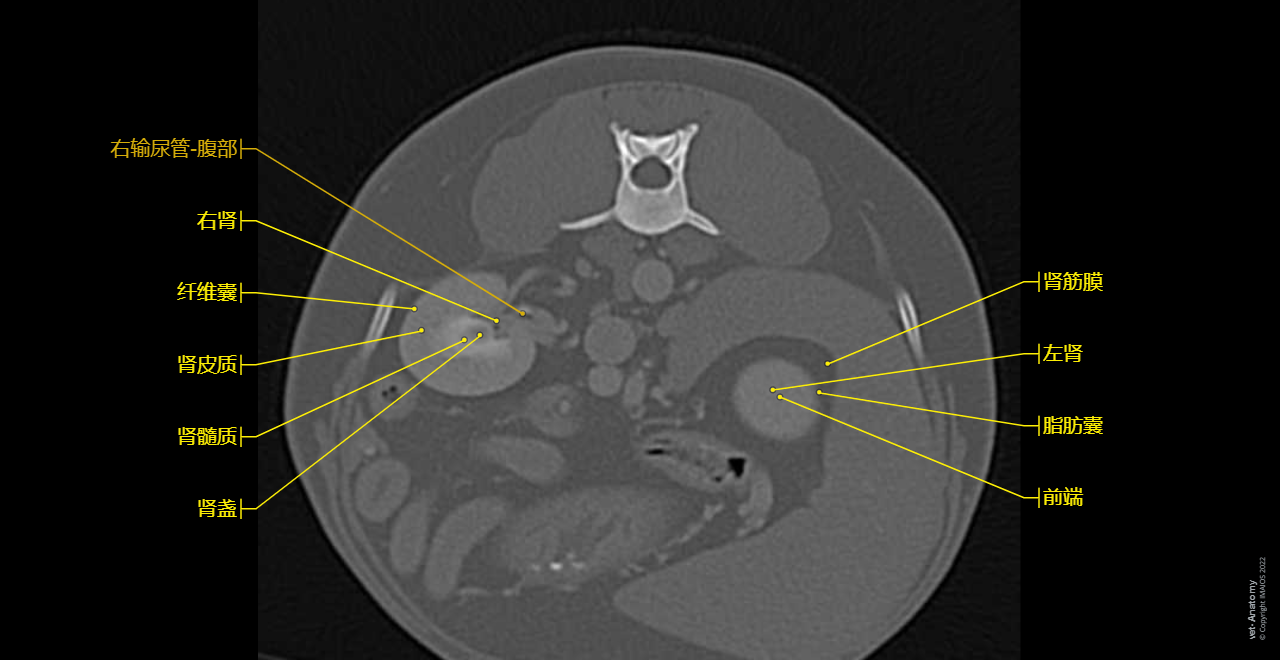

vet-Anatomy兽医图集的本模块是关于CT扫描的犬类腹部和骨盆。

CT图像来自一只健康的6岁阉割雄性犬。

在vet-Anatomy动物图集的此模块中,计算机断层扫描(CT)显示了标有解剖结构的犬科腹腔和骨盆横截面,并用3D图像显示犬科腹部。

CT图像存在3个平面方向(横向,矢状和背侧),并且使用两种对照方式(软组织/血管和骨骼)展现。本模块的末尾提供其他3D解剖图像,便于进一步了解犬科总体解剖结构,展示了骨骼、内脏(肝脏、脾脏、胰腺、消化道)、泌尿生殖系统、动脉、全身静脉系统(主要是尾腔静脉及其分支)、门静脉系统、肌肉和表面解剖的三维容积透视图。

Dog - Urinary organs: Kidney, Ureter, Urinary bladder, Male urethra

Kidney - Dog - Anatomy atlas

Dog

Kidney